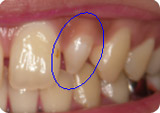

側切歯(前から2番目の歯)の形態が異なります。青丸部分![]()

また上顎側切歯には尖状歯(歯が円錐状の形をしている)とよばれる形態異常が時々認められます。

上顎側切歯(上の前から2番目の歯)と下顎第2小臼歯(下の前から5番目の歯)に最も多く認められます。